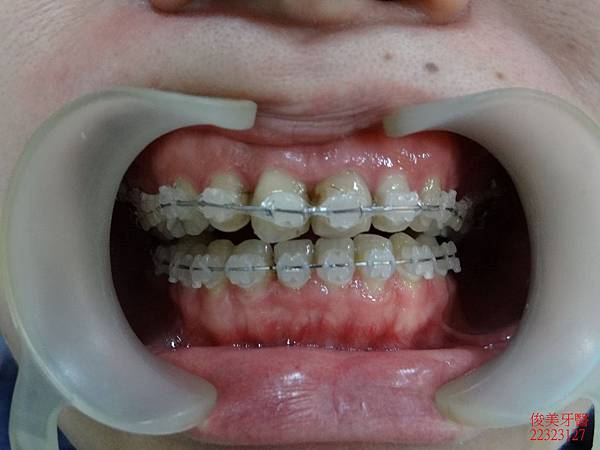

治療中~~~~

將牙齒牙根移到正確的位置。

沒有重疊的現象。

之前已將右側智齒拔除,僅留左側供咀嚼。